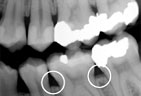

Gum disease is usually caused by plaque, a sticky film of bacteria that constantly forms on teeth. If plaque is not removed with thorough daily brushing and cleaning between teeth, gums become irritated and inflamed. The irritated gum tissue can separate from the teeth and form spaces called pockets. Bacteria move into the pockets where they continue to promote irritation. Left untreated, the process can continue until the bone and other tooth-supporting tissues are destroyed. The early stage of periodontal disease is called gingivitis. It often results in gums that are red and swollen and may bleed easily.

Advanced Periodontitis Advanced Periodontitis